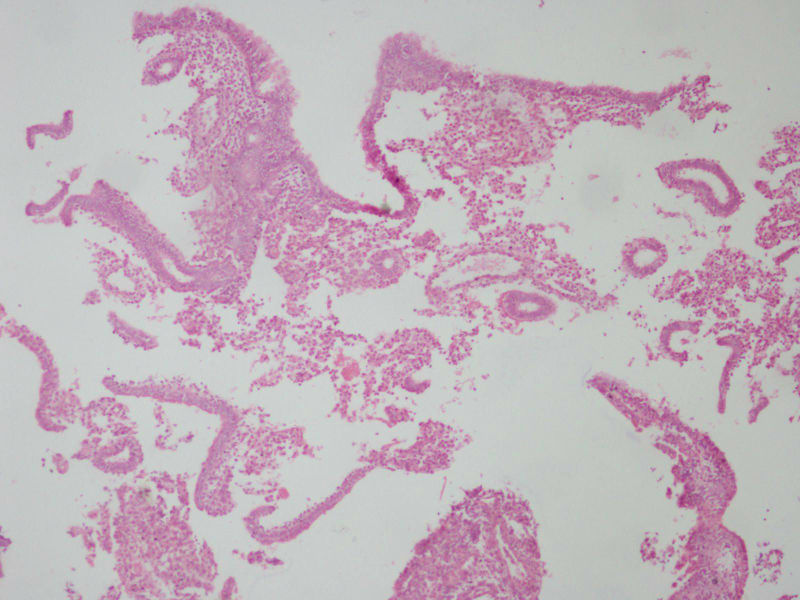

女

27

结婚

2

年未避孕未怀孕停经

4

月